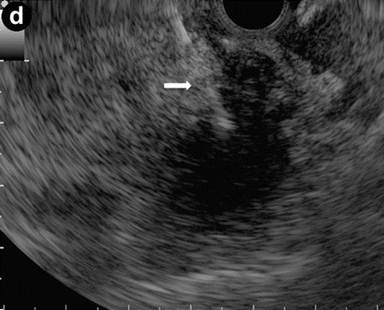

A 43-year-old woman with recurrent abdominal pain, jaundice and elevated levels of IgG4 (264 mg/dL). Transabdominal US and CT showed an enlarged pancreatic head, slightly dilated intra-hepatic bile ducts with a stricture of the intra-pancreatic common bile duct, and a distal focal stricture of the main pancreatic duct. Intraductal sonography performed during ERC revealed that the common bile duct stenosis was due to bile duct wall thickening (arrows) (Image 7), with a "sandwich-pattern".

Image 7 |

EUS-guided biopsies are effective in obtaining bile duct samples for cytological and histological examinations; intraductal sonography can help in characterizing biliary stenosis. In this setting, intraductal sonography shows concentric bile duct wall thickening with a smooth configuration of the outermost layer, similar to that seen on EUS imaging [11]. This inflammatory thickening represents the biliary involvement of autoimmune pancreatitis; it is the cause of bile duct stenosis detected by CT, ERCP, MRCP and it responds to steroid therapy [11].

The "sandwich-pattern" of the common bile duct wall can be a pivotal EUS feature for diagnosing autoimmune pancreatitis. On the other hand, the biliary involvement of biliary or pancreatic carcinoma is characterized by EUS as the presence of an echopoor, transmural lesion with irregular borders involving the duct wall.